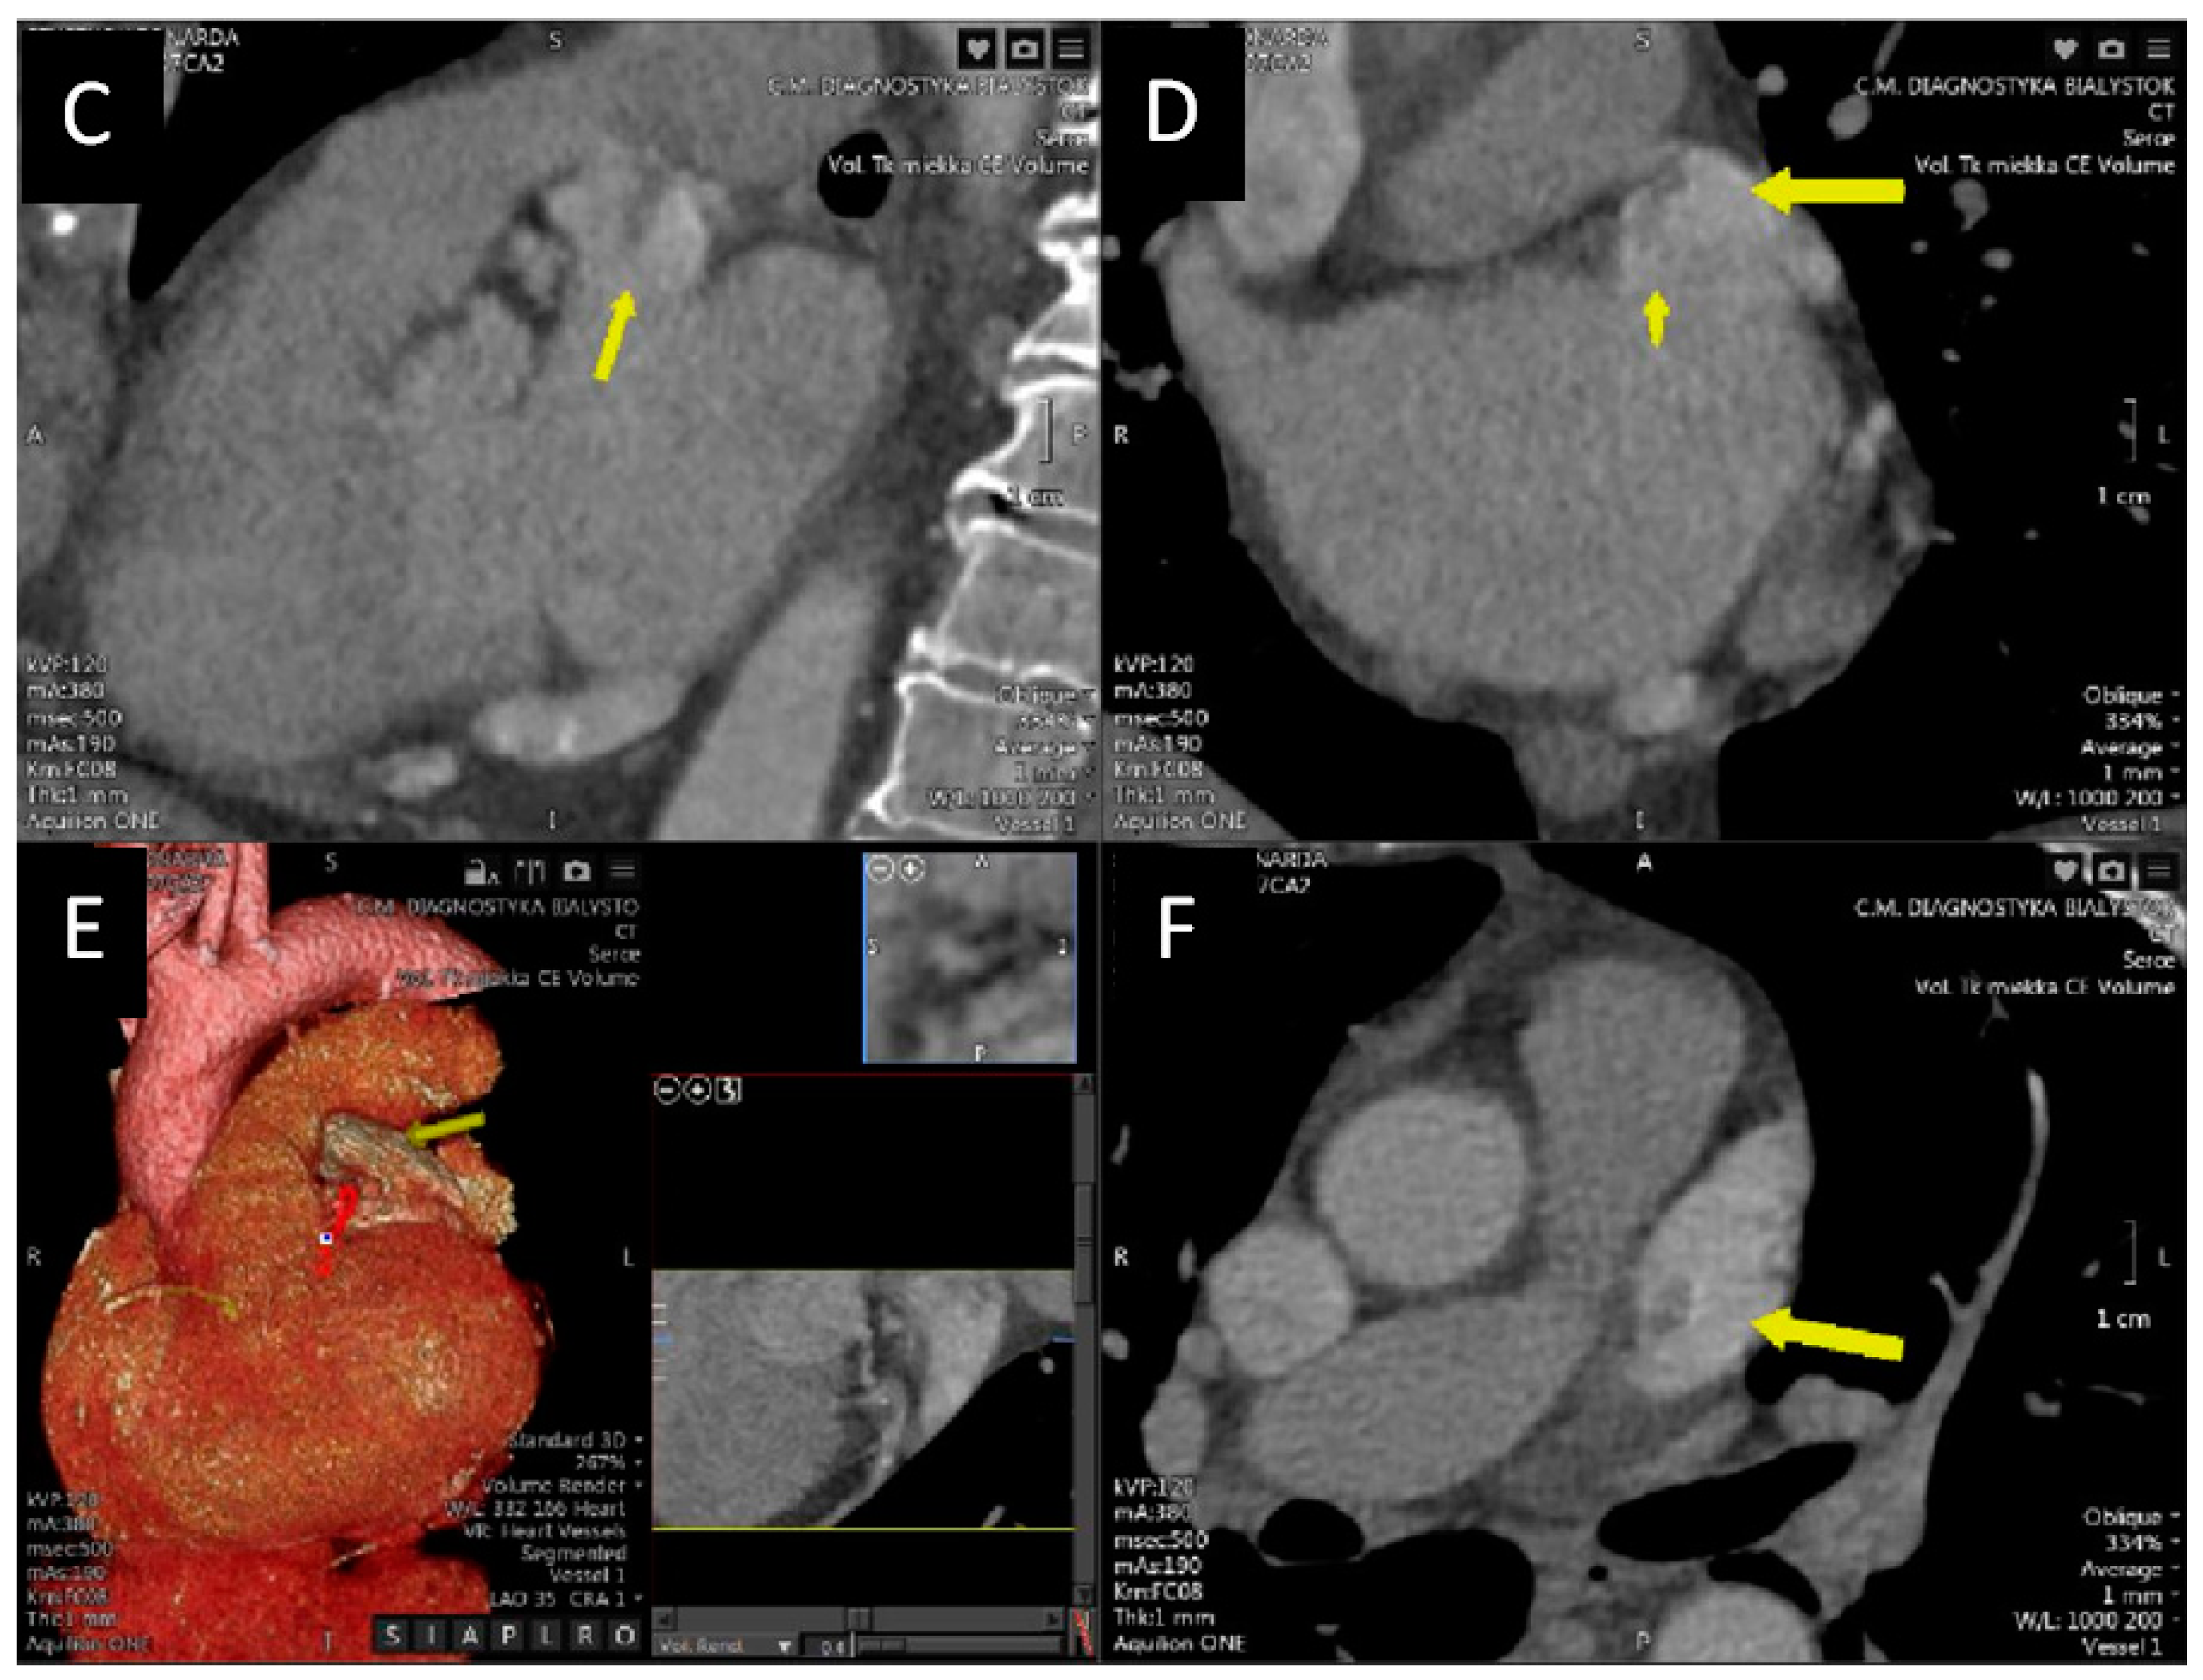

Echocardiography, Computed Tomography and Magnetic Resonance Imaging in the Differential Diagnosis of a Tumor in the Left Atrium of the Heart